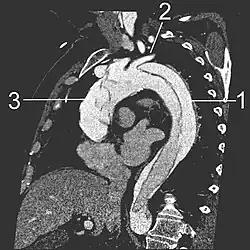

| Computertomografie (CT) | Legende |

| Aortendissektion Typ Stanford A 1 Aorta ascendens, wahres Lumen – 2 falsches Lumen – 3 Lungenschlagader 4 Aorta descendens – 5 Brustwirbelkörper | |

Eine mit Kontrastmittel durchgeführte CT gestattet eine umfassende und exakte Darstellung der gesamten Aorta und kann sowohl die Dissektion selbst als auch deren räumliche Beziehung zu den Seitenästen der Aorta und eventuelle Blutungen in der Umgebung zuverlässig darstellen. Eine mögliche Beteiligung der Aortenklappe ist allerdings nicht erkennbar, die klappennahen Aortenabschnitte sind auf Grund von Artefakten durch das schlagende Herz bei älteren CT-Geräten schwieriger zu beurteilen. Mit diesen Geräten wurde in mehreren Studien eine Sensitivität von 83–94 % und eine Spezifität von 87–100 % ermittelt, moderne Spiral-CT erreichen eine Sensitivität von durchschnittlich mehr als 95 %.